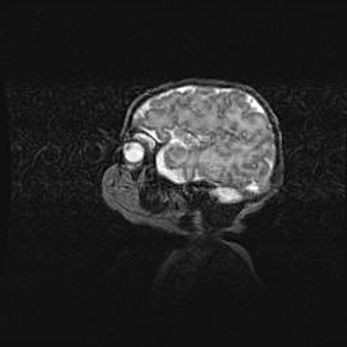

Подострая гематома правой гемисферы мозжечка.

Наружная гидроцефалия.

Возраст: 15 дней

Вес: 3100 г

Пол: женский

Окружность головы: 37 см

Срок гестации: 35-36 недель

При открытой наружной форме гидроцефалии у новорожденных расширяются и переполняются субарахноидные пространства.

Кровоизлияния в мозжечок имеют две клинико-анатомические формы: полушарные гематомы и кровоизлияния в червь.

К появлению этой патологии может привести: повреждения головного мозга, возникающие в результате асфиксии и гипоксии плода при беременности, или травмы во время родов. Редко гематома мозжечка может быть результатом первичной коагулопатии и сосудистой мальформации, диссеминированном внутрисосудистом свертывании, изоиммунной тромбоцитопении.